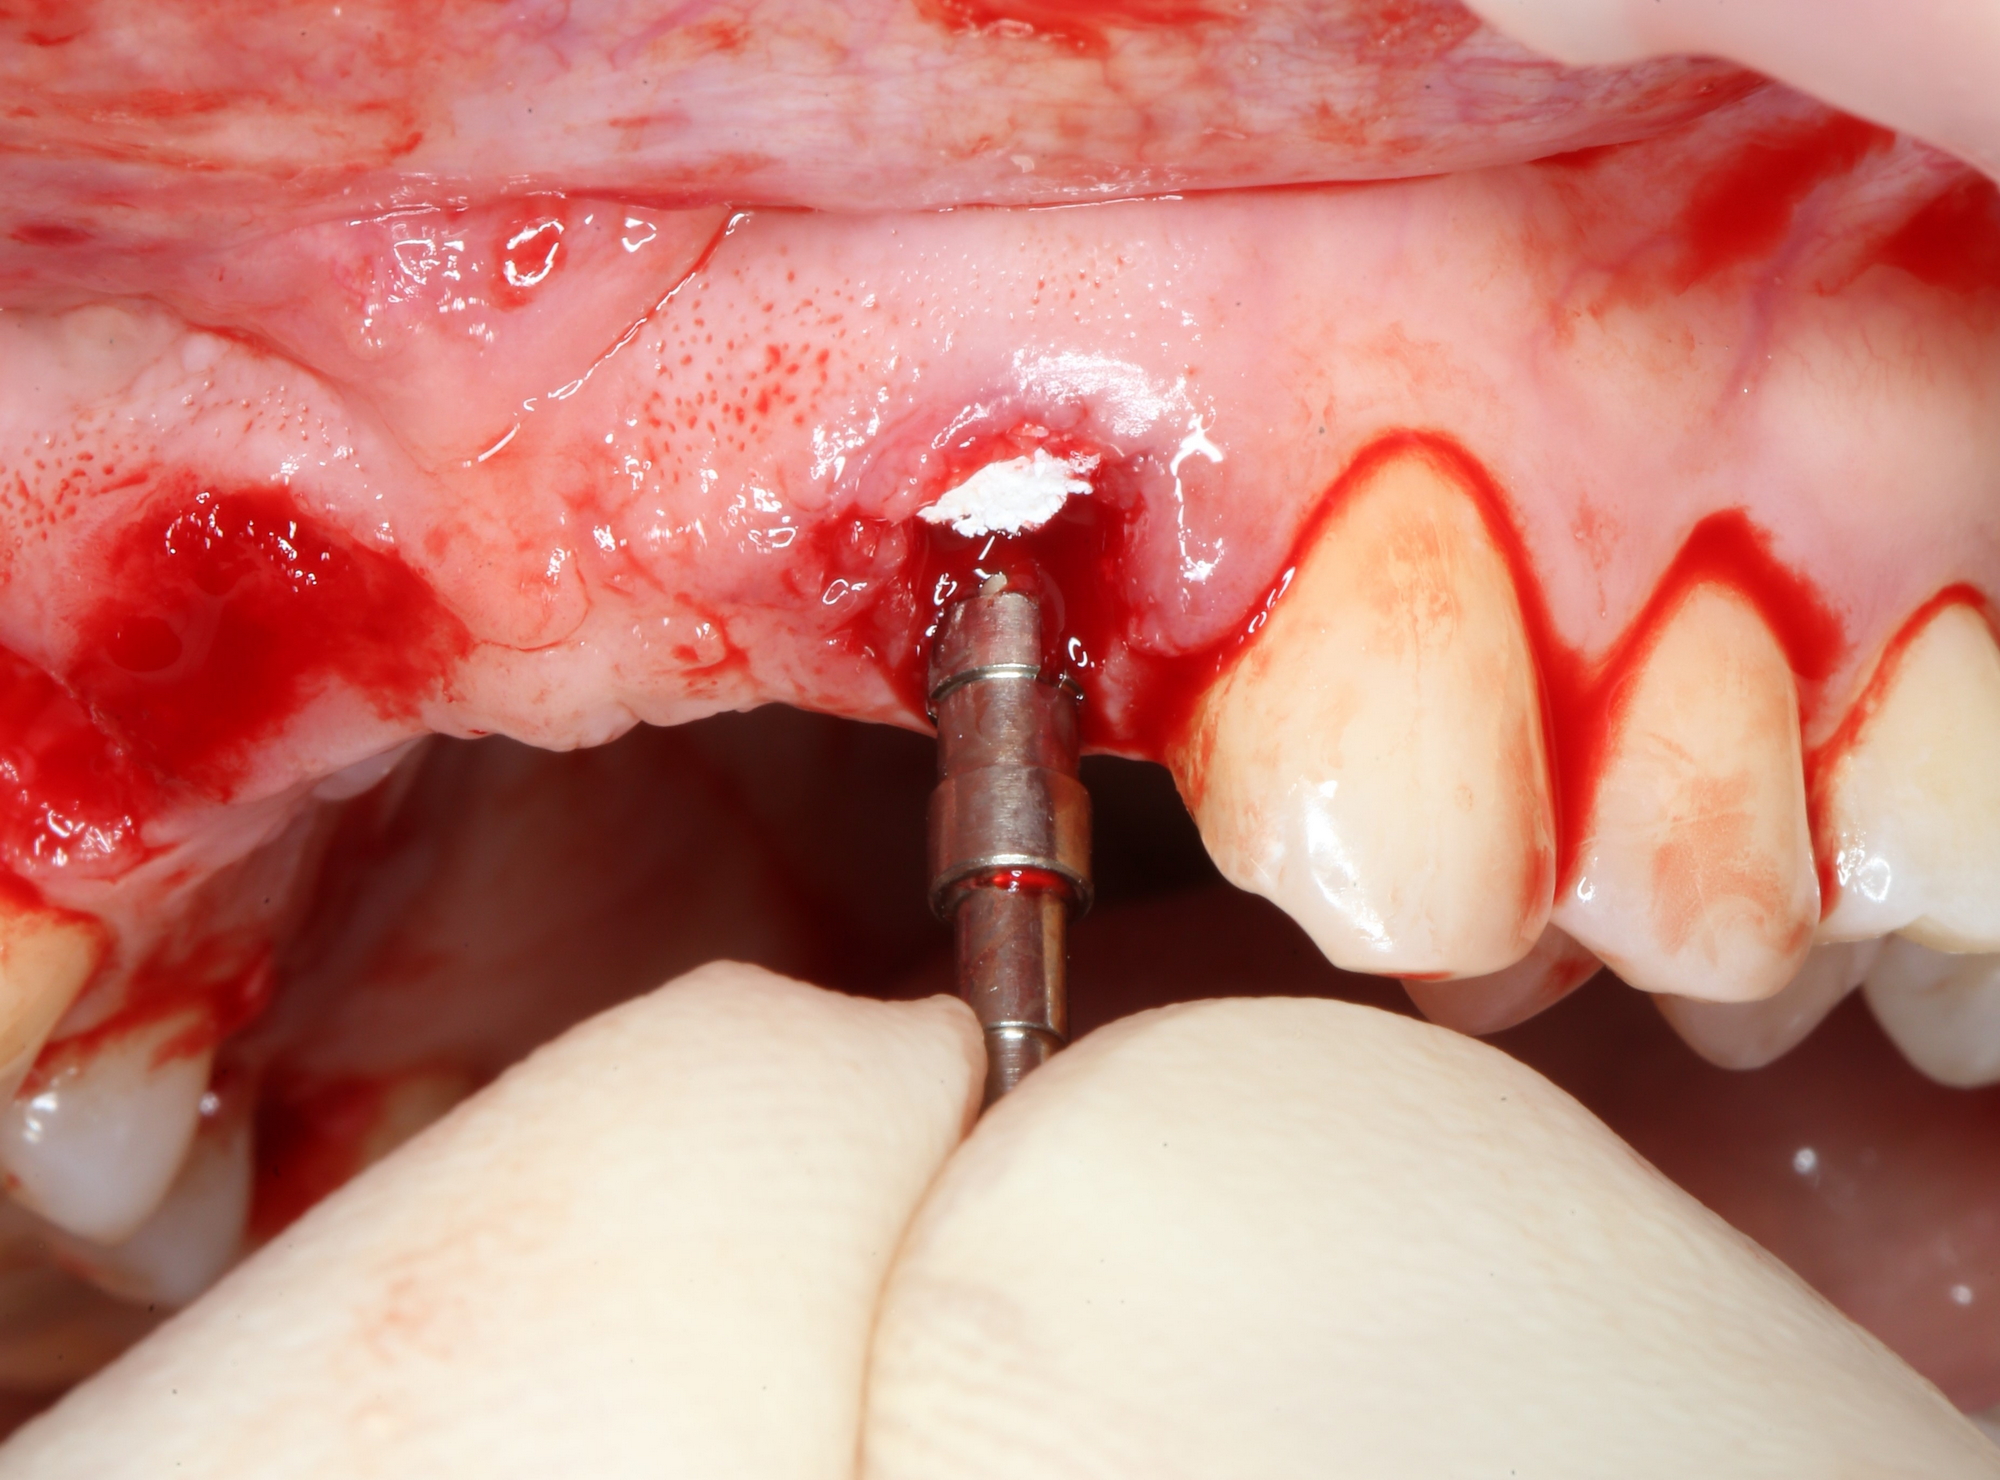

С имплантационной системой Xive это очень просто сделать — в наборе есть аналоги имплантатов, поэтому мы готовим лунки последовательно, перекрёстно ориентируясь установленным аналогам. Напомню, мы планируем винтовую фиксацию будущего протеза, поэтому правильное положение имплантатов является критически важным для успешной реализации нашего плана:

О правильном позиционировании и подборе имплантатов можно почитать здесь>>, не видим смысла пускаться в подробности. На фото выше — правильное положение имплантатов (ну, или аналога и фрезы) в области боковых резцов.

можно установить имплантат. Напомню, мы выбрали Xive S диаметром 3.4 и длиной 13 мм:

Далее, мы повторяем все эти действия с лункой 12 зуба — аугментация с помощью Bio-Oss Collagen, паковка с помощью аналога имплантата, установка имплантата Xive 3.4х13 мм: